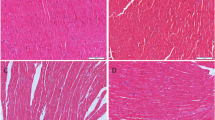

Animal and CIHH treatment

Sixty adult male Sprague–Dawley rats (weight 300–350 g), obtained from the Animal Center in Hebei Medical University, were randomly divided into 2 groups: control group and CIHH treatment group (CIHH). The rats in control group were kept in the same environment as CIHH rats except hypoxia exposure. Body weight of rats was measured at a fixed time weekly. All rats were housed at room temperature with a natural light: dark cycle (12 h:12 h), and had free access to water and food.

Effect of CIHH on heart weight

The body weight of rats increased during the period of the experiment and there was no significant difference in body weight between control and CIHH rats (P > 0.05, Table 1). The ratios of ventricle weight to whole body weight (VW/BW), left ventricle weight to whole body weight (LV/BW), right ventricle weight to whole body weight (RV/BW), and right ventricle weight to left ventricle weight (RV/LV) in CIHH rats were unchanged significantly compared with those in control rats (P > 0.05, Table 2).